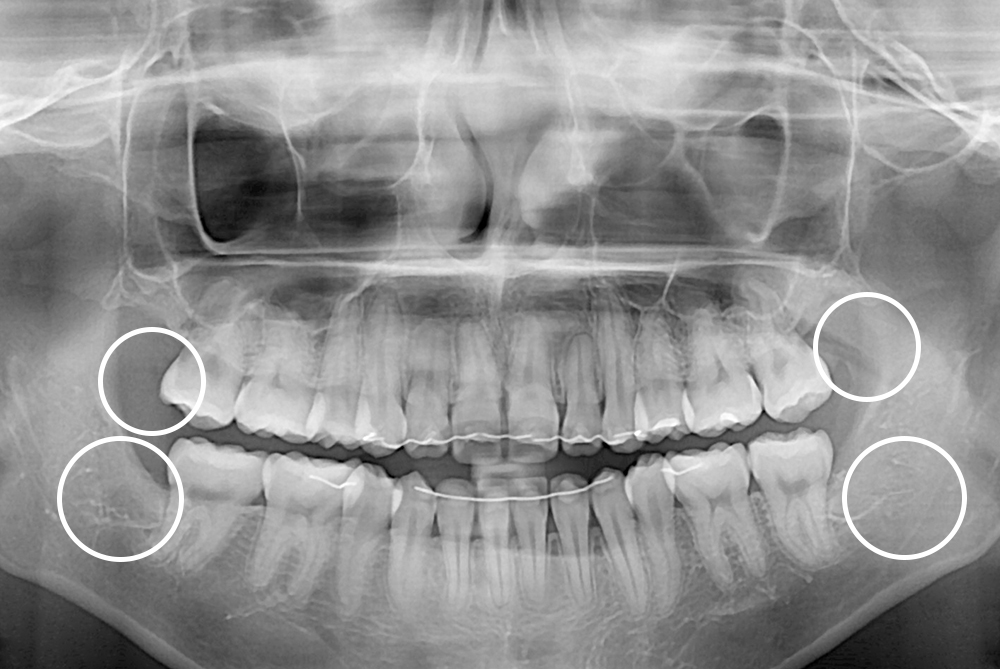

[사랑니] 매복 사랑니 발치

치료전 : 2019-02-08